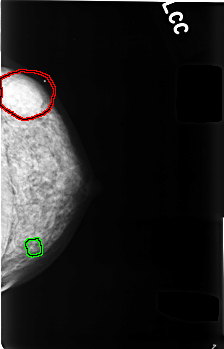

C_0480_1.LEFT_CC

LEFT_CC LINES 4536 PIXELS_PER_LINE 2912 BITS_PER_PIXEL 12 RESOLUTION 50 OVERLAY

FILE: C_0480_1.LEFT_CC.OVERLAY

TOTAL_ABNORMALITIES 2

ABNORMALITY 1

LESION_TYPE MASS SHAPE ROUND MARGINS MICROLOBULATED

ASSESSMENT 3

SUBTLETY 5

PATHOLOGY BENIGN

TOTAL_OUTLINES 1

BOUNDARY

ABNORMALITY 2

LESION_TYPE CALCIFICATION TYPE DYSTROPHIC DISTRIBUTION CLUSTERED

SUBTLETY 3